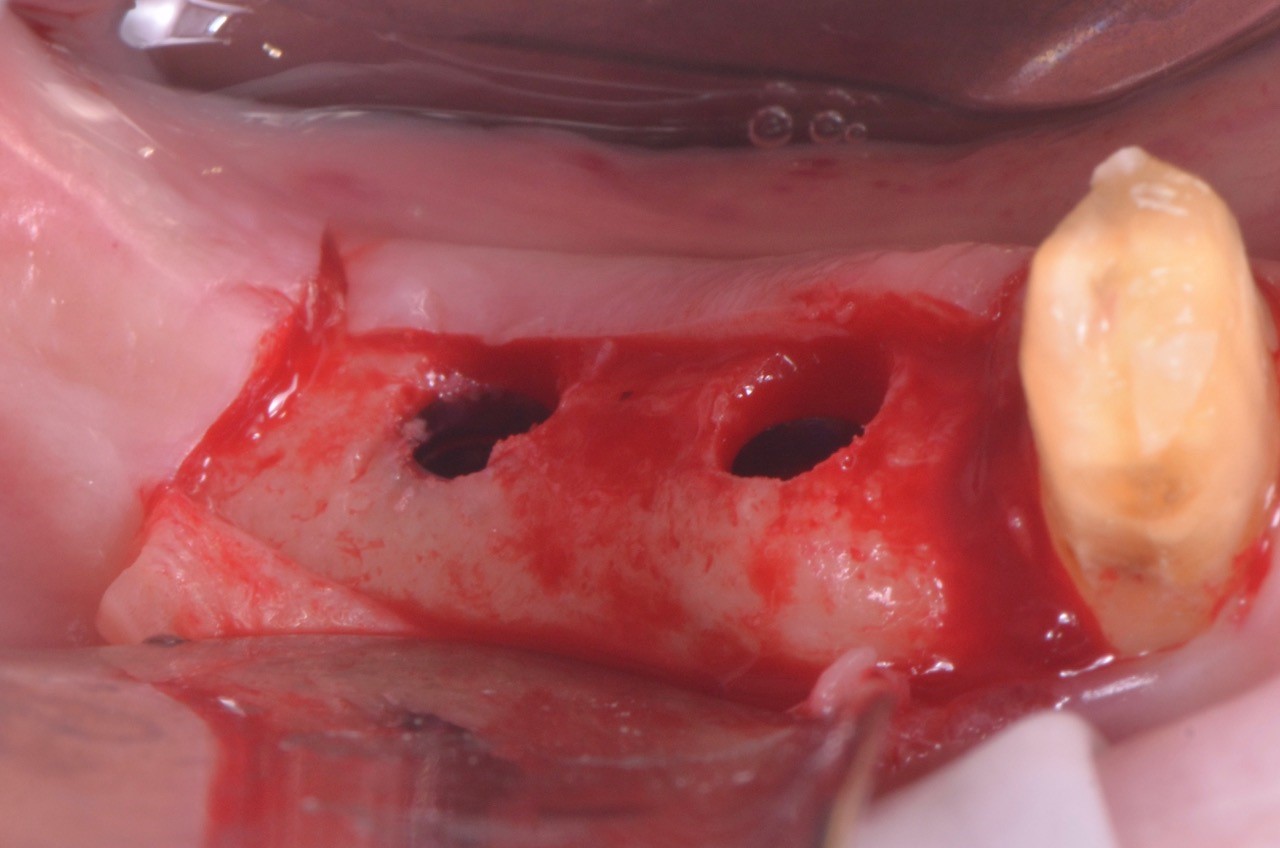

Foto: Posizionamento subcrestale di due impianti MIS V3